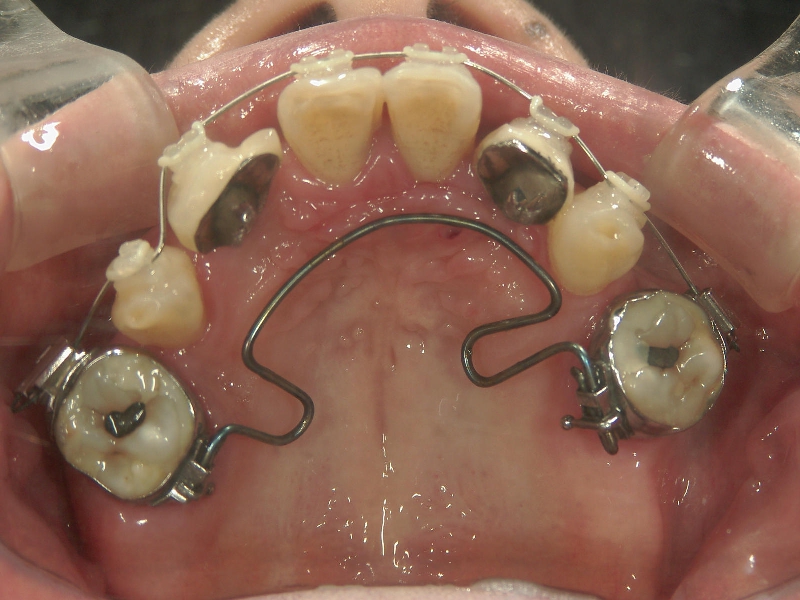

● 臼歯部の後方移動

臼歯を後方に牽引し、移動させることでスペースを確保し歯列を整えます。

抜歯矯正をした経験があり、新たに抜歯

できる歯がないため、臼歯を後方へ牽引

してスペースを確保します。

臼歯にリンガルアーチという装置を装着し、ミニインプラントを固定源に臼歯を後方に牽引します。

臼歯が後方に下がり、臼歯と小臼歯の間にスペースができました。唇側にワイヤ-をSETし、前歯の歯並びの改善を併行して行います。